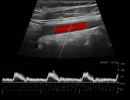

- Έγχρωμο Doppler: Αξιολογεί την ταχύτητα και την κατεύθυνση της ροής του αίματος, προσδιορίζοντας την ύπαρξη και το ποσοστό στένωσης των αρτηριών.

- Παλμικό Doppler: Παρέχει πληροφορίες για τις διακυμάνσεις της ροής του αίματος, βοηθώντας στην αναγνώριση πιθανών αιμοδυναμικών διαταραχών.